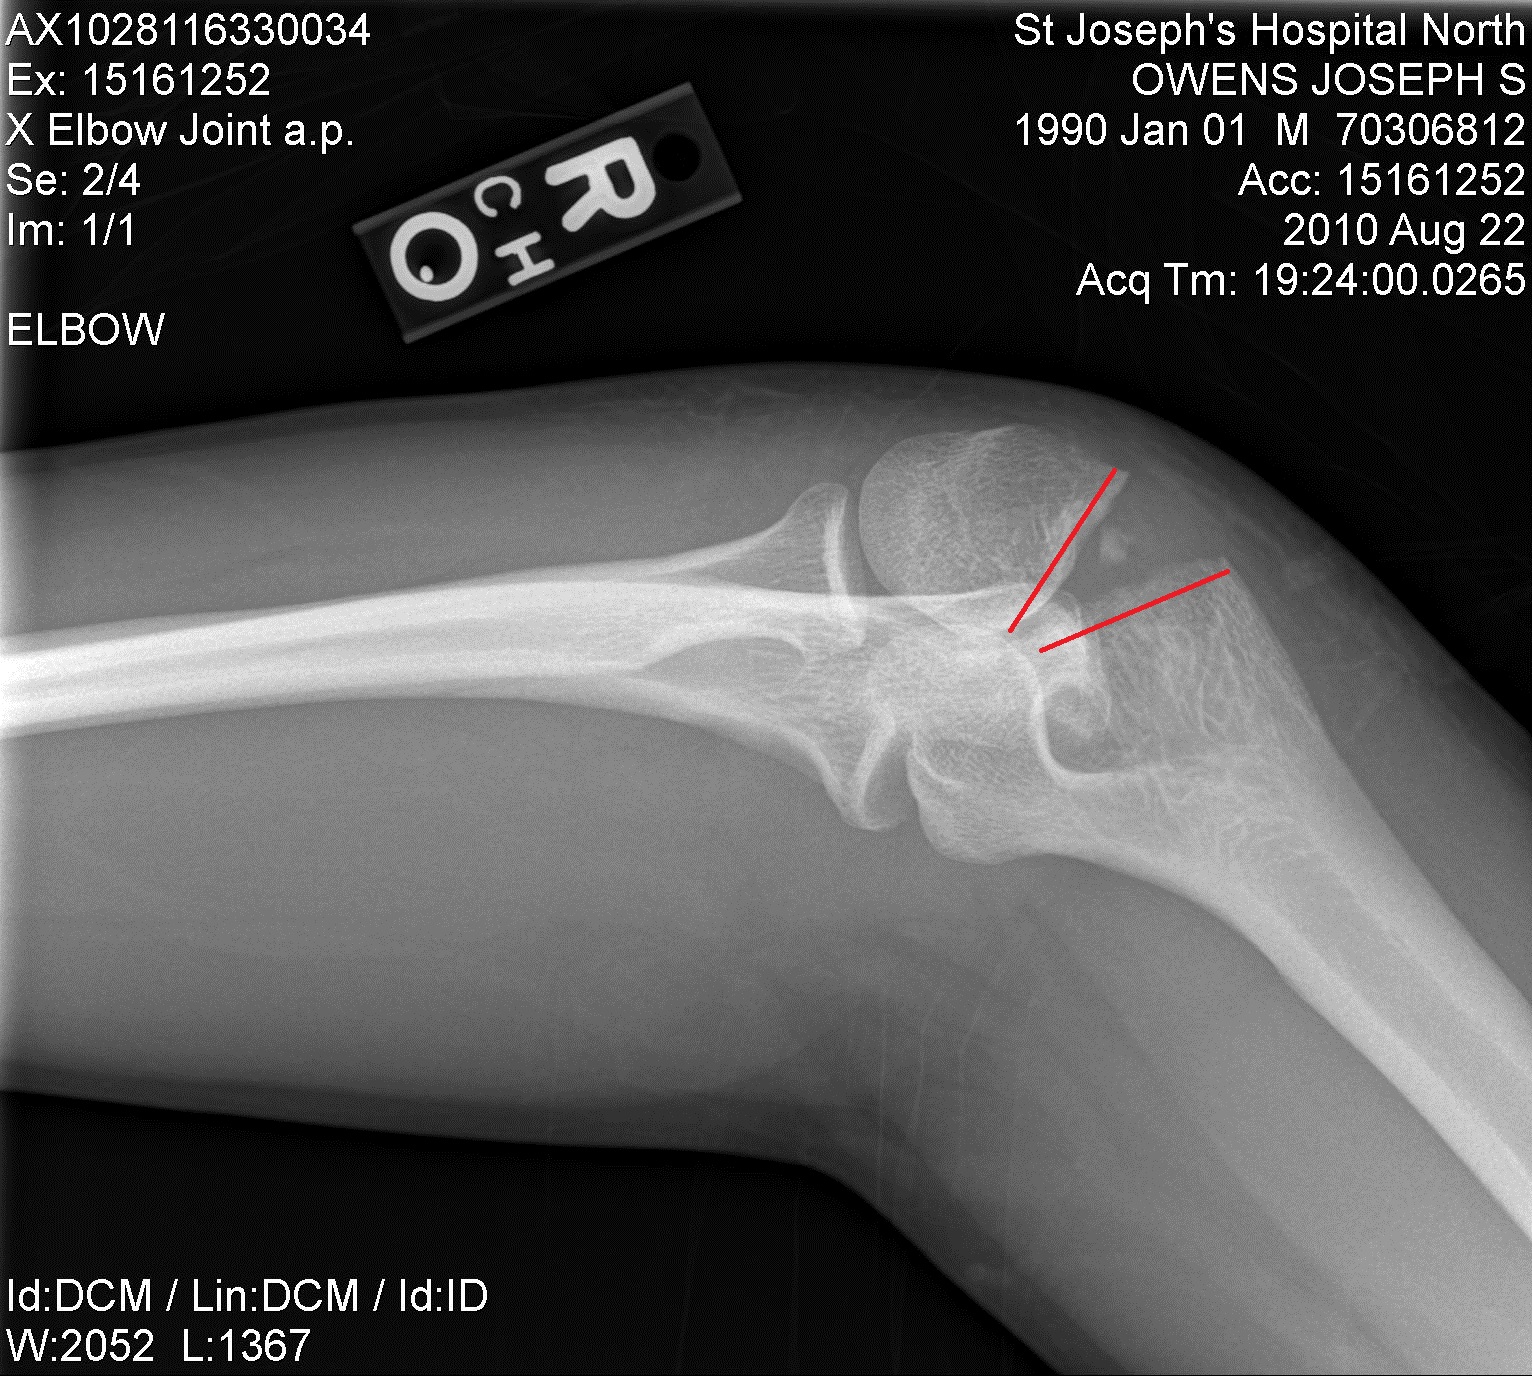

From www.alamy.com

Broken elbow. Xray of the arm of a 44 year old female patient with a Broken Elbow Tips  Learn about the symptoms, treatment and healing of a fracture of the upper end of your radius near the elbow. Learn how physical therapy can help you recover from a broken elbow and prevent stiffness and weakness. Learn about the causes, symptoms, diagnosis, treatment, and recovery of a broken elbow, a fracture of one or more of the three bones. Broken Elbow Tips.